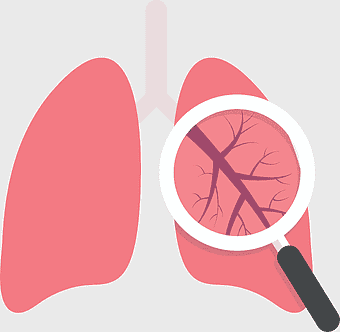

Pulmonary edema symptoms, chronic obstructive pulmonary disease diagram, kidney failure effects on lungs, pulmonary circulation illustration, lung disease diagnostic, respiratory health visuals, human anatomy respiratory system, PNG

- pulmonary edema symptoms

- chronic obstructive pulmonary disease diagram

- kidney failure effects on lungs

- pulmonary circulation illustration

- lung disease diagnostic

- respiratory health visuals

- human anatomy respiratory system

Lung transplantation, pulmonary health, interstitial Lung Disease, magnifying medical diagnosis, respiratory treatment, lung care awareness, airway observation -